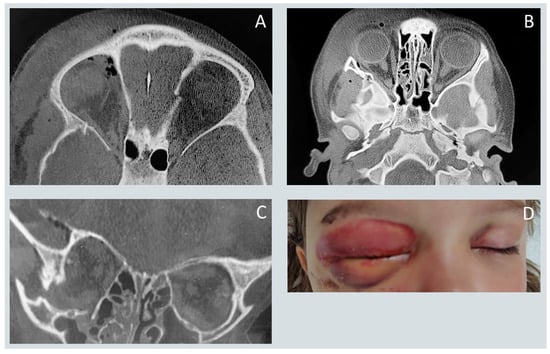

Pediatric Maxillofacial Fractures: Patterns of Injury, Surgical Indications, and Treatment Outcomes: A Five-Year Retrospective Study

Background: Pediatric craniofacial fractures represent a distinct clinical entity characterized by unique anatomical and developmental factors that differentiate them from adult facial trauma. Despite their relative rarity, these injuries pose diagnostic and therapeutic challenges due to the presence of active growth centers and [...] Read more.

Background: Pediatric craniofacial fractures represent a distinct clinical entity characterized by unique anatomical and developmental factors that differentiate them from adult facial trauma. Despite their relative rarity, these injuries pose diagnostic and therapeutic challenges due to the presence of active growth centers and the potential for long-term functional and esthetic sequelae. Methods: A retrospective observational study was conducted among pediatric patients aged 0–17 years treated for craniofacial fractures between 2020 and 2024 at the Department of Cranio-Maxillofacial Surgery, University Hospital in Kraków, Poland. Demographic data, injury mechanisms, fracture distribution, treatment modality, and associated injuries were analyzed. Multivariate logistic regression was applied to identify predictors of surgical intervention. Results: Ninety-eight patients met the inclusion criteria. The mean age was 12 years, with a male predominance. Midfacial fractures were most common, with orbital floor fractures representing the single most frequent injury. Surgical management was performed in 72 cases, predominantly using the transconjunctival approach and autologous bone grafting. Orbital floor fractures were identified as the only independent predictor of operative treatment (p < 0.05). Central nervous system trauma was the most frequent concomitant injury. No significant changes in etiology or fracture distribution were observed during the COVID-19 pandemic. Conclusions: Pediatric craniofacial trauma follows a reproducible, age- and mechanism-dependent pattern. Effective management requires individualized, growth-preserving, and function-oriented treatment strategies. Standardization of care protocols and multicenter prospective studies are essential to optimize outcomes and develop evidence-based, age-specific guidelines for the management and prevention of pediatric facial fractures. Full article